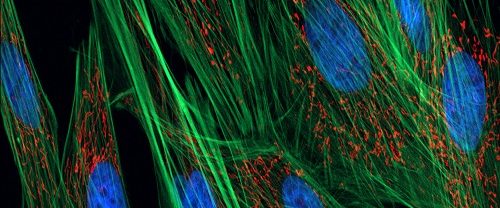

Fibroblast Nedir ve Ne İşe Yarar? Fibroblastlar, bağ dokusunun ana hücreleri olarak bilinen ve vücudumuzun çeşitli bölgelerinde bulunan önemli hücrelerdir. Bağ dokusunun yanı sıra deri, tendonlar, kıkırdak ve kemikler gibi yapıların oluşumunda da görev alırlar. Kollajen, elastin ve diğer yapısal proteinlerin üretiminden sorumludur. Fibroblast Hücreleri ve İşlevleri: Bağ doku içinde yer alır ve yassı bir…